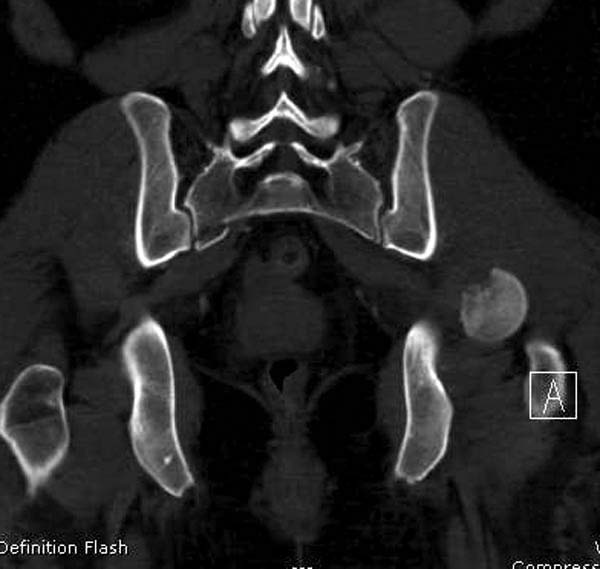

Женщина 28 лет, политравма.

По протоколу обследования больных с травмой сделаны все исследования и выставлен диагноз: разрыв печени и селезенки; множественные переломы ребер и лицевого черепа; стабильный перелом позвоночника, переломо-вывих головки левого бедра, перелом диафиза правого бедра, переломо-вывих правого тарана.

----------- следущая часть -----------

Вложение не в текстовом формате было извлечено&hellip;